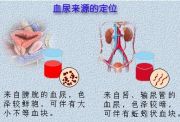

| 2021年7月26日 (一) 20:03 | 血尿来源.jpg (文件) |  |

45 KB | Uploaded with SimpleBatchUpload | 3 |